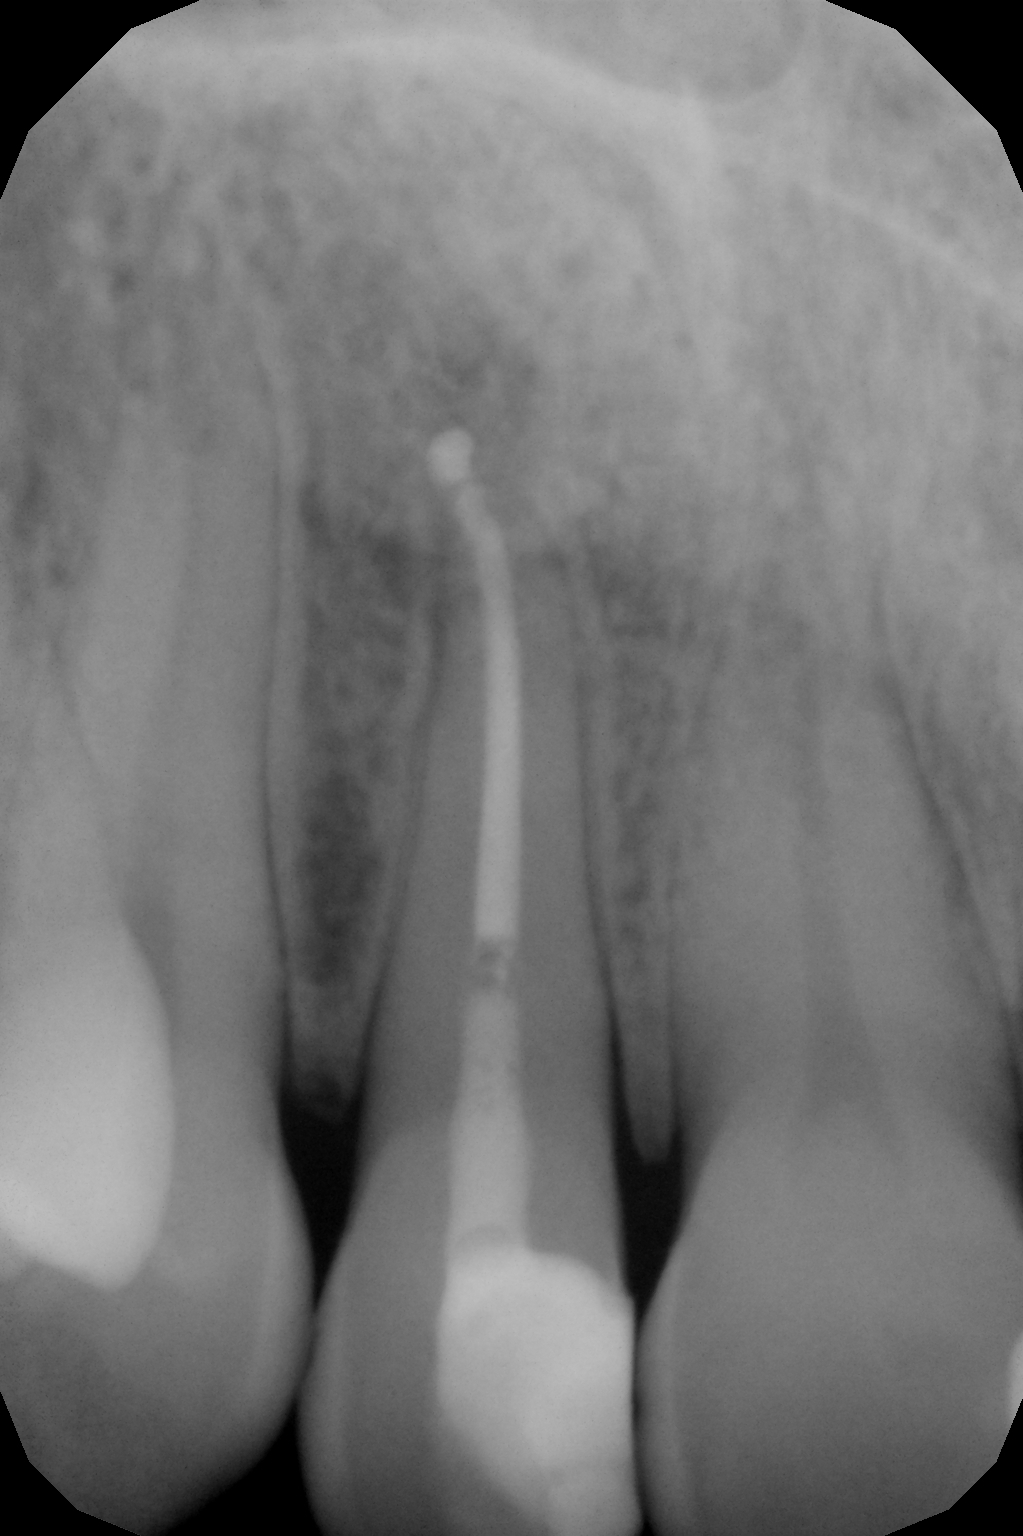

LASER TERAPIA

Dai multipli effetti chirurgico, emostatico, decontaminante, biostimolante.

- decontaminazione dei canali endodontici